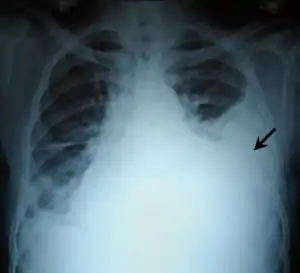

| Other names: Haemothorax Hæmothorax Haemorrhagic pleural effusion | |

![]() | |

| Chest X-ray showing left sided hemothorax (arrowed) | |